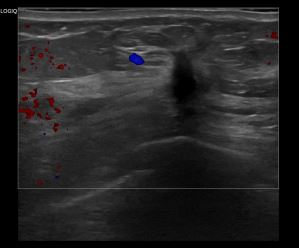

아산유외과개원후 947번째 유방암진단

상기환자는 외부검사 이상소견으로 조직검사 권유받아 내원하신 50대 후반 여성분으로 의심스러운 좌측 혹 조직검사 시행해 유방암 진단 되었습니다